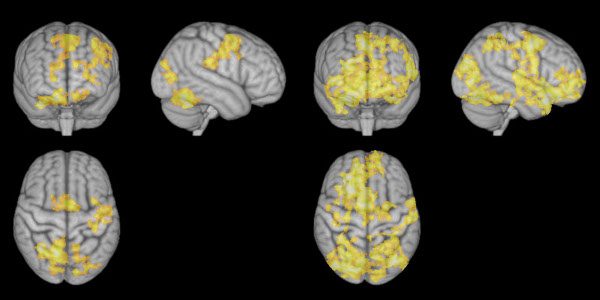

Imaginile din stânga arată creierul în timpul unei meditaţii de concentrare, în timp ce imaginile din dreapta arată creierul în timpul unei meditaţii non-directive. Credit: Norwegian University of Science and Technology.

Meditaţia non-directivă a cauzat participanţilor la test o activitate cerebrală mai intensă decât în cazul în care aceştia se odihneau, în special în regiunile cerebrale dedicate prelucrării gândurilor şi sentimentelor. Atunci când subiecţii de test au practicat o meditaţie de concentrare, activitatea cerebrală în acea parte a creierului a fost aproape la fel ca şi atunci când se odihneau.